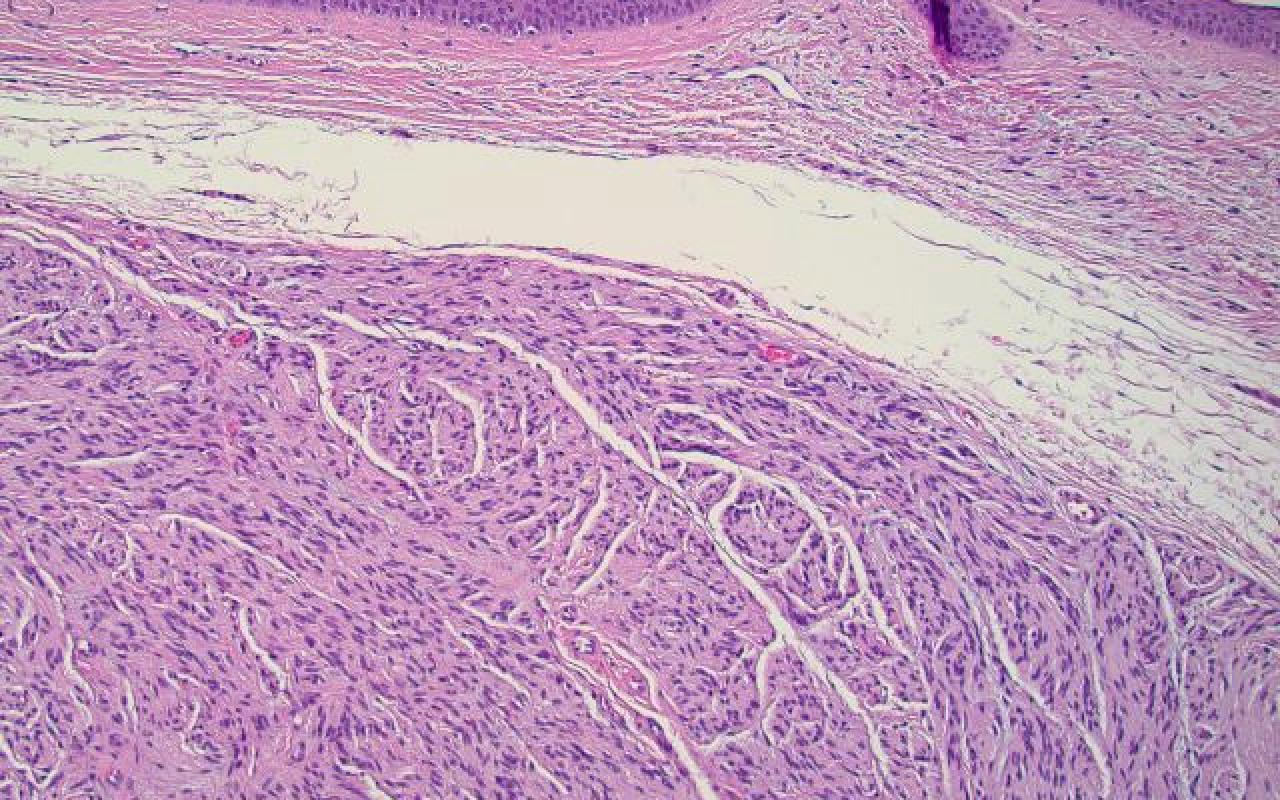

Q

Correct choice: B. Fibrosarcomatous tumor

Explanation: This best describes the fibrosarcomatous type of dermatofibrosarcoma protuberans. It has a high rate of recurrence and is associated with a poor prognosis. They are also CD34+ and wide excision is recommended.